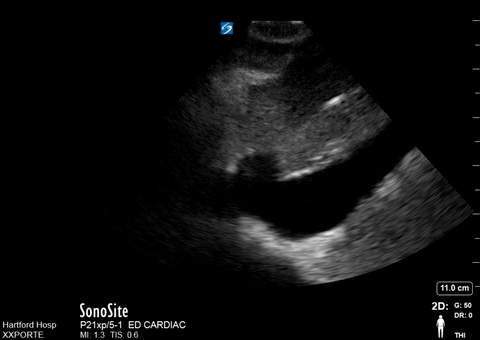

Plethoric IVC ultrasound

| current | 11:19, 25 July 2016 | 480 × 340 (1.45 MB) | Neil.m.young (talk | contribs) | Plethoric IVC ultrasound |